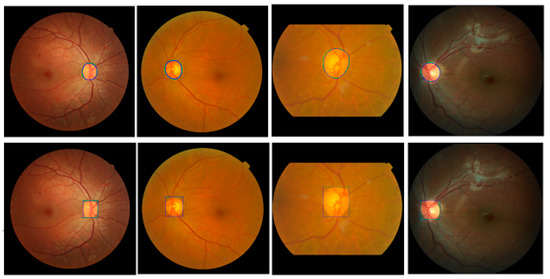

Mask R-CNN is used to segment the optic disc from the fundus images to estimate the ROI. To train the model, we augment each training image into ten using a vertical flip and five rotations (−20°, −10°, 0°, 10°, and 20°) to increase the number of images in the training dataset. Since ten-fold cross-validation is adapted, ten training/test sets are used in this experiment. In each training set, 80% of the images are used for training and 20% are for validation. Input images are reshaped to a square shape (1200 × 1200). We use ResNet101 as a backbone, five backbone strides (4, 8, 16, 32, and 64), epochs = 100, batch size = 1, learning rate = 0.001, learning rate2 = 0.0001, learning momentum = 0.9, and weight decay = 0.001 to train the network. For the Region Proposal Net (RPN), we use three RPN anchor ratios (0.5, 1.0, and 2.0), five RPN anchor scales (128, 192, 256, 184, and 512), and the RPN non-max suppression (NMS) threshold = 0.7. Equal weights are used for the Mask R-CNN class, Mask R-CNN bounding box, and Mask R-CNN mask losses for the optimization of the model. Figure 8 shows the results using images from four different datasets. Green is GT data and blue is the proposed Mask R-CNN output. The top row shows outputs of the optic disc boundary, and the bottom row shows ROI outputs. Although there is a small discrepancy between the GT data and the Mask R-CNN outputs, the outputs show relatively accurate results. Overall, the proposed Mask R-CNN shows 0.9037 JI, 0.9489 DC, 0.9231 Sensitivity, 0.9996 Specificity, and 0.9983 Accuracy.

Figure 8.

Examples of the proposed Mask R-CNN Results. Top row shows output of optic disc boundaries. Bottom row shows output of ROIs. Green is ground-truth data and blue is estimated Mask R-CNN results.